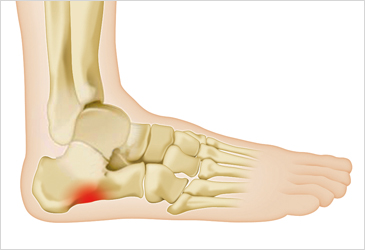

이 질환은 발밑의 족저근막에 염증이 생겨 발뒤꿈치에서 발가락까지 이어지는 섬유띠가 영향을 받는 질환으로, 중장년층 뿐만 아니라 젊은 세대에게도 흔하게 발생합니다.

족저근막염은 다양한 원인이 있습니다. 발의 구조적인 이상인 평발이나 요족 등이 원인일 수 있지만, 대부분은 발을 과도하게 사용하여 발생합니다.